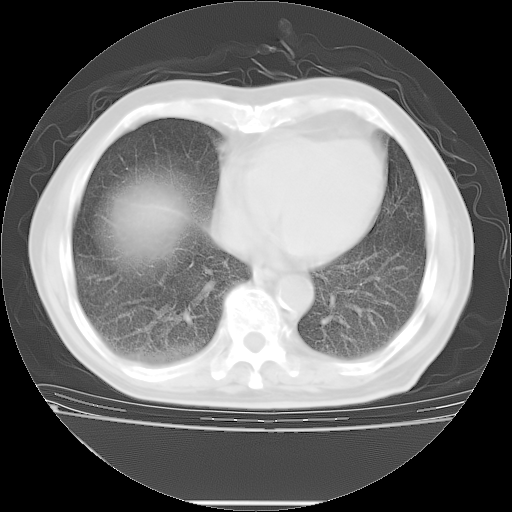

今天复查肺部CT,发现双肺广泛磨玻璃样改变。所以我把3月19日和5月9日相隔50天的肺部CT上传。请大家会诊。

2009年3月19日肺部CT片。

2009年3月19日肺部CT